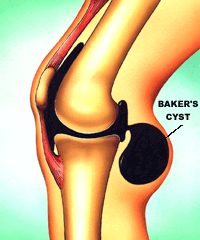

Фото и диагностика кисты Бейкера